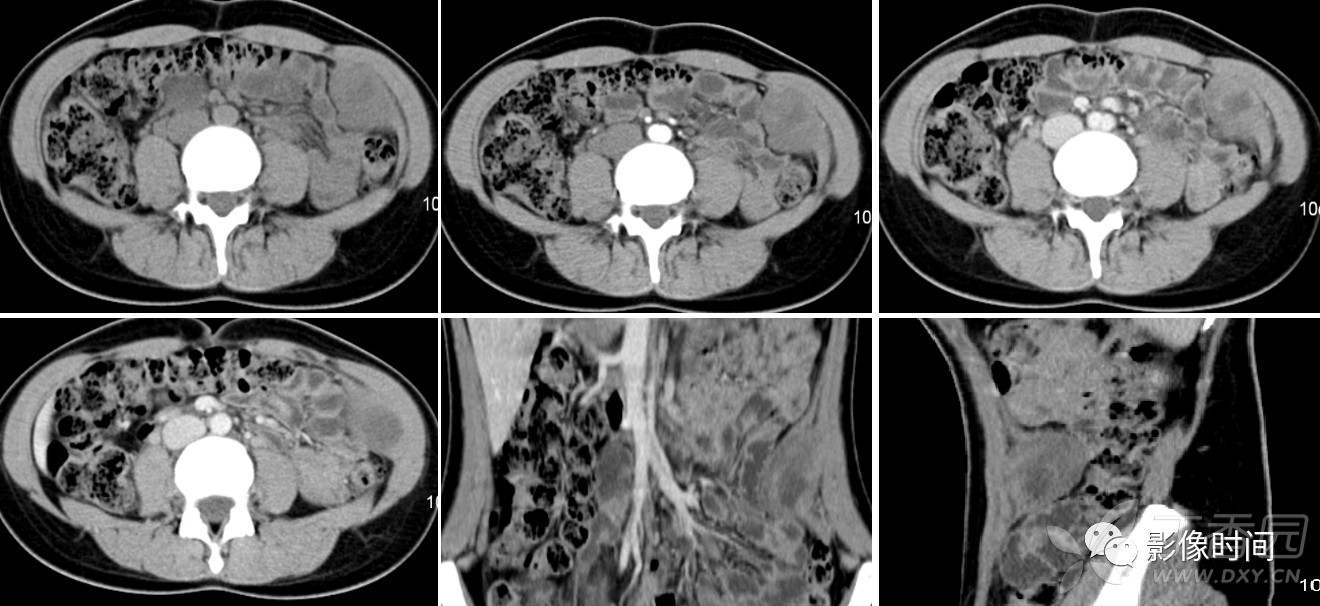

右腹壁肿物---韧带样型纤维瘤病